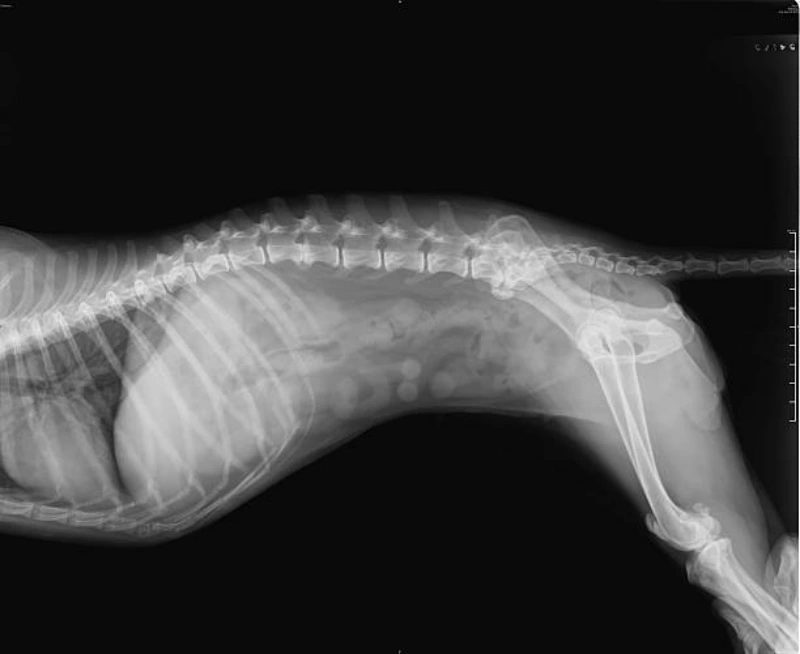

O raio x veterinario valor é fundamental para a saúde dos animais, pois permite a visualização de estruturas internas que não são visíveis a olho nu.

A radiografia é um exame não invasivo que fornece informações precisas sobre ossos, órgãos e tecidos, auxiliando no diagnóstico de diversas condições, como fraturas, tumores, problemas cardíacos e respiratórios.

Além disso, o raio x é essencial para o acompanhamento de tratamentos e monitoramento de doenças crônicas, assegurando o bem-estar dos pets.

A radiologia veterinária é uma área diagnóstica que utiliza exames de imagem, como o raio X, para identificar alterações internas no organismo dos animais.

Esse recurso permite visualizar ossos, órgãos e tecidos de forma não invasiva, auxiliando no diagnóstico de fraturas, tumores, alterações cardíacas e problemas respiratórios.

O exame é rápido, preciso e fundamental para que o veterinário defina o tratamento mais adequado.

Além de contribuir em casos emergenciais, também é utilizado em avaliações de rotina e acompanhamento de doenças crônicas.